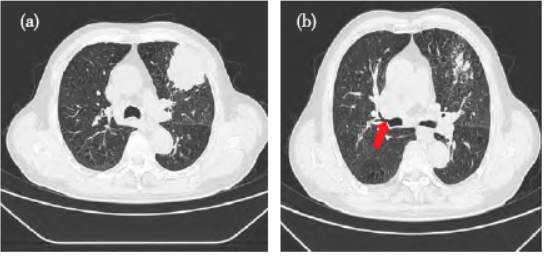

胸部CT(图1a)示左肺上叶前段巨大占位,考虑周围型肺癌,邻近左侧第3 肋骨受侵破坏,两肺肺气肿

伴渗出。此次入院拟行“胸腔镜左上肺切除+淋巴结清扫+肋骨切除+胸壁占位切除+胸壁成形”术。目前,对于具有永久气管造口病人行OLV 的最佳肺隔离方式尚无定论。

图1 病人胸部CT 检查结果。注:a:CT 显示左上肺巨大占位,直径48 mm×38 mm;b:CT 显示右上叶开口(红色箭头)正常,无变异。